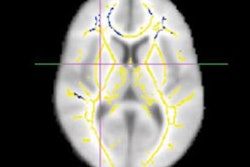

A federal court has ruled that diffusion-tensor MRI (DTI-MRI) scans are not "junk science" and are admissible in court as evidence of traumatic brain injury (TBI).

This argument was rejected by the U.S. District Court for the Southern District of Florida, which found that DTI results have been deemed reliable and admissible by courts around the U.S. for almost 10 years. What's more, DTI has been subject to peer review and publication, and it is generally seen as an acceptable method for TBI detection.